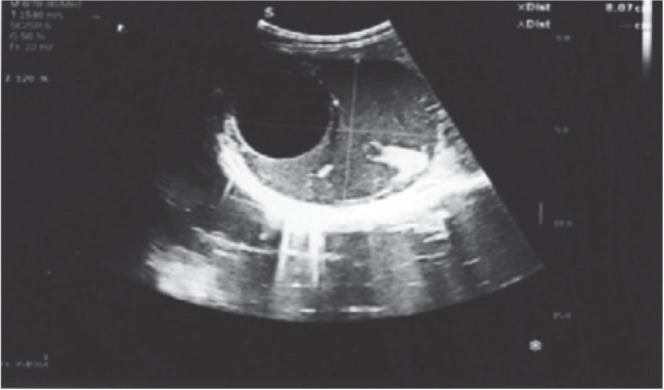

This case report presents a 43-year-old worker (welder in the locksmith trade) from Bosnia and Herzegovina who was diagnosed with advanced hydatidosis during a preventive medical examination. The patient had a history of frequent close contact with dogs at home and at work and reported a long-standing sensation of heaviness in the left side of his abdomen. As part of his routine occupational health examination, he had a complete laboratory testing, abdominal ultrasound, multislice computed tomography (MSCT), and a consultation with an infectious disease specialist and abdominal surgeon. Imaging revealed multiple cystic formations in the left hemiabdomen and a cyst in segment VIII of the liver, confirming the diagnosis of multivisceral echinococcosis. The patient was promptly treated with preoperative (and postoperative) albendazole to reduce the cyst size and prevent complications. This case highlights the critical role of ultrasound in the diagnosis of hydatidosis, especially in an occupational medicine context. As part of preventive screening, ultrasound is a valuable tool for the early detection of echinococcosis in workers in high-risk environments. Early diagnosis allows for timely intervention, reducing the risk of disease progression to an advanced stage. This case underscores the importance of implementing effective epidemiological strategies, including regular screenings and awareness campaigns, in order to control the spread of echinococcosis in endemic regions.

本病例报告涉及一名来自波斯尼亚和黑塞哥维那的43岁工人(锁匠行业的焊工),他在预防性医学检查中被诊断患有晚期包虫病。患者有在家和工作中经常与狗密切接触的病史,并报告其左腹部长期有沉重感。作为常规职业健康检查的一部分,他做了完整的实验室检查、腹部超声、多层计算机断层扫描(MSCT),并咨询了传染病专家和腹部外科医生。影像学显示左半腹多发囊性形成,肝脏第八节段一囊肿,确认多脏器包虫病的诊断。患者术前(术后)及时使用阿苯达唑治疗,以减小囊肿大小并预防并发症。本病例强调超声在包虫病诊断中的关键作用,特别是在职业医学背景下。作为预防性筛查的一部分,超声是在高危环境中早期发现棘球蚴病的宝贵工具。早期诊断可以及时干预,减少疾病进展到晚期的风险。这一病例强调了实施有效的流行病学战略的重要性,包括定期筛查和提高认识运动,以控制棘球蚴病在流行地区的传播。